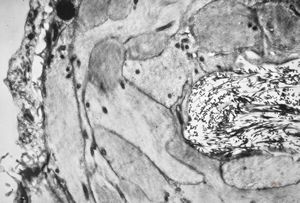

rabbit spinal cord trauma

rabbit spinal cord trauma